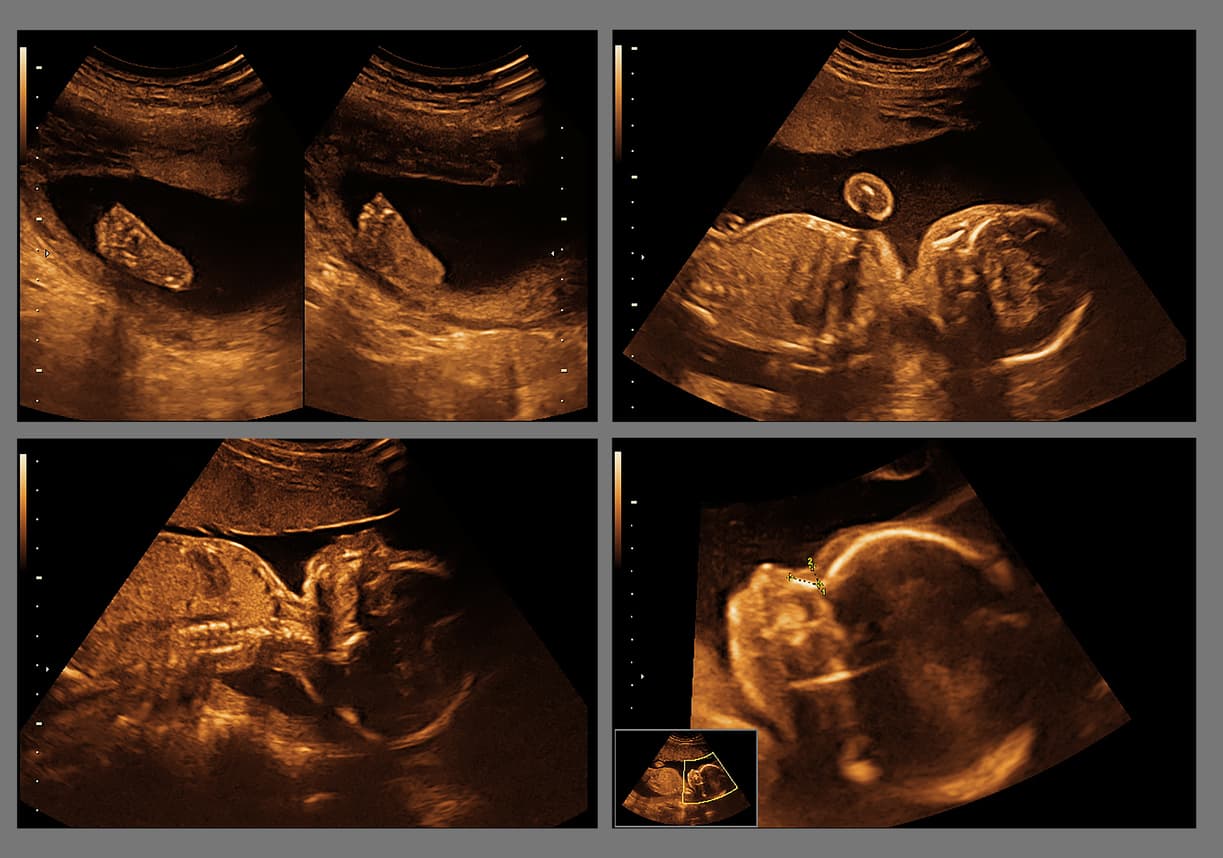

WebMD confirma que gracias a la ecografía y otras herramientas de alta tecnología se han logrado conocer varios datos curiosos sobre la vida en el vientre de mamá.

Según un artículo publicado en PLOS One los bebés sí pueden bostezar en el vientre de mamá. Quince fetos sanos fueron escaneados cuatro veces a las 24, 28, 32 y 36 semanas de gestación y los captaron bostezando. Lo mejor de todo es que dicho movimiento es un indicador de desarrollo fetal sano, según los especialistas.

Un estudio publicado en el 2011, también en la revista de divulgación científica PLOS One, demuestra que luego de la semana 33 de gestación tu pequeño tiene la capacidad de realizar las expresiones faciales propias del llanto, como fruncir el ceño y mover la boca, pero no hay forma de que puedas escucharlo.